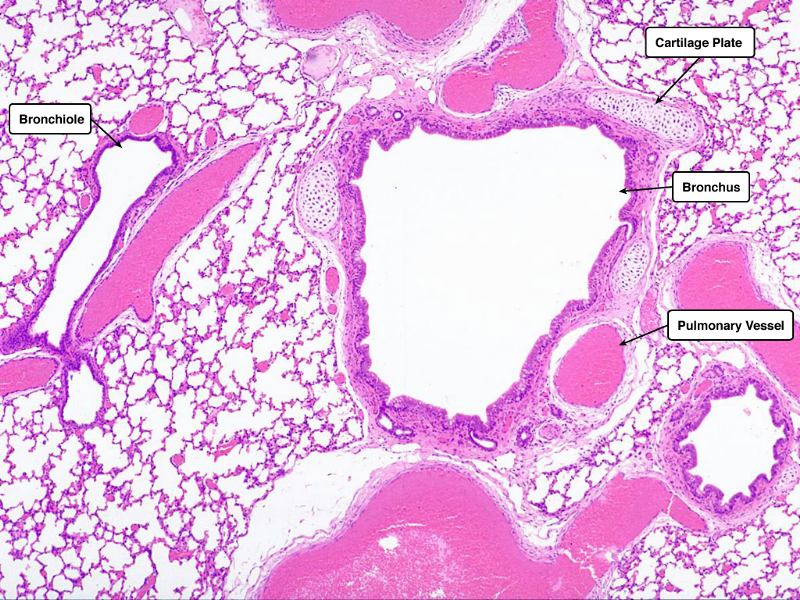

Trace the air flow of respiratory system starting with the nostrils.

What path does a molecule of oxygen take to reach the blood?

What sights will it see along the way?

- Outside air

- ??

- ...

- Toes

Path of O2

- List complete

- With layers

- And cells

- And function of each

- By studying and labelling images

Identify and describe the epithelium on the following slide: